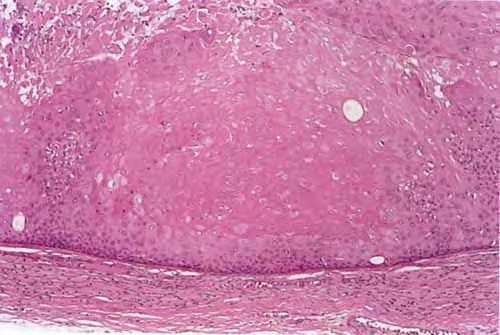

Proliferating trichilemmal cyst = كيسة غمد الشعرة التكاثرية